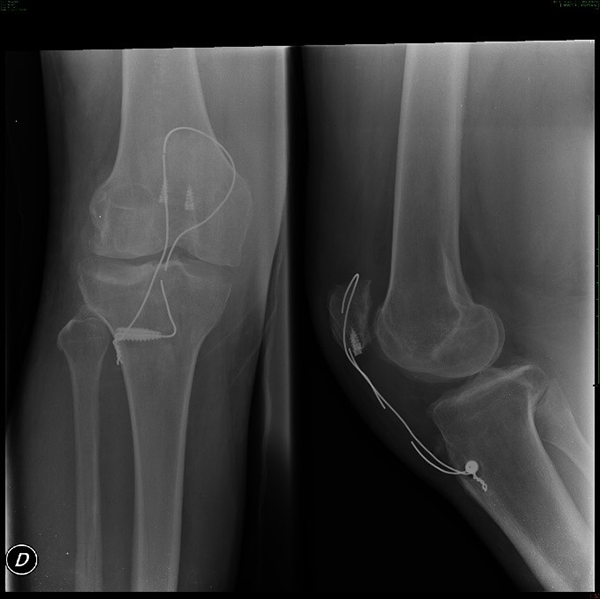

El seguimiento a los ocho meses mostró que el paciente alcanzó la marcha sin apoyo con un rango de movimiento funcional, tanto para la flexión como para la extensión, comparativa con la contralateral (figs. 8 a 11).

Figura 8: Radiografía de control postquirúrgico a los ocho meses (se observa ruptura del cerclaje).